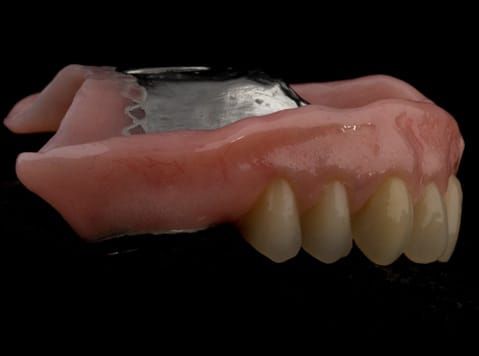

- Cobalt chromium reinforced gasket denture - using a Molloplast B "O" ring to retain and stabilise the denture. This was my professional preference as this was the least invasive and simplest solution to this dental problem. Should the UR7 require removal in the future - an artificial tooth could be added - resulting in a complete denture. The patient would have adapted to the denture fully by this stage and have good neuromuscular control of the prosthesis.

Following consultation and second discussion appointment the patient chose to have option 2 namely, a window denture - maxillary cobalt chromium based partial denture. The clinical situation and treatment process is shown in detail below with photographs. The patient was successfully rehabilitated with this and her quality of life considerably improved. The clinical work was provided by Finlay and the technical work by Rowan.